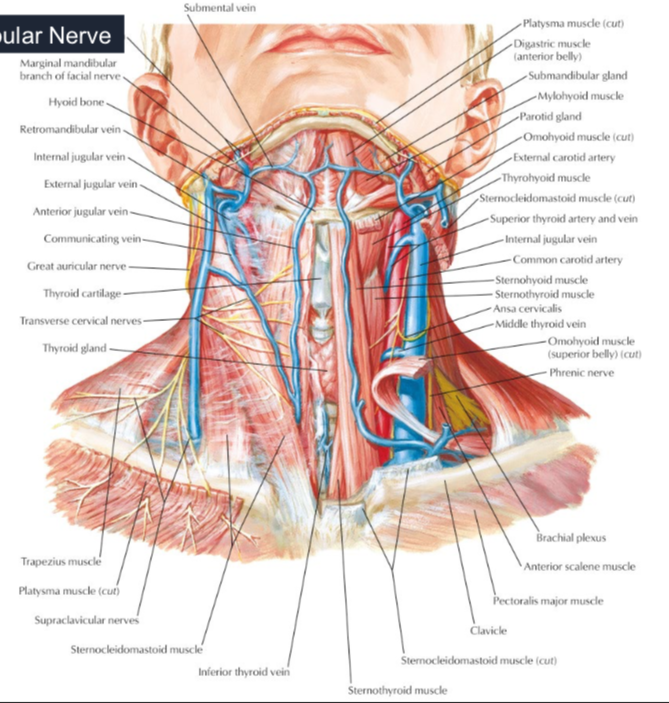

SCM血液

上1/3

中1/3

- Sup. thyroid a.

- Ext. carotid a.

下1/3

- suprascapular a. (>80%)

subclavian vein 在ant. scalene m. 上方

- common carotid a. 外側,蓋在 thyrocervical trunk 上